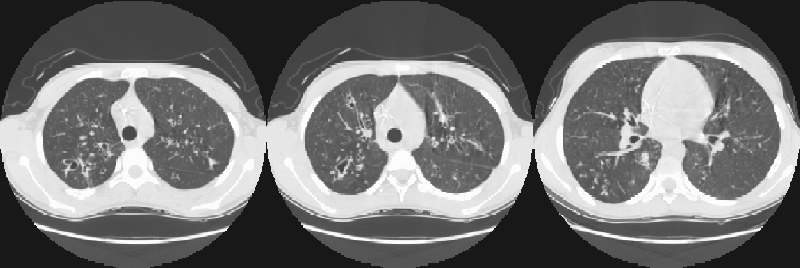

Scott WilliamsPETPET > PET tumor imaging > GeneralApril 2, 2002PETPET > PET tumor imaging > Head and Neck TumorsApril 2, 2002PETPET > PET tumor imaging > Lung CancerApril 2, 2002Infection-InflamationInfection-Inflammation > Genitourinary > Testicular imagingApril 2, 2002CongenitalCongenital > CF > Images > Cf1April 2, 2002Cardiac ImagingCardiovascular > Thallium > Thallium imagingApril 2, 2002PleuraPleura > ChylothoraxApril 2, 2002AutoimmuneAutoimmune > PanbronchitisApril 2, 2002Miscellaneous PulmonaryMisc > Bronchiolitis > Images > Case1April 2, 2002Miscellaneous PulmonaryMisc > Mediastinum > Images > Case2April 2, 2002Previous PagePage 83 of 265Next PageTop StoriesRadiation Oncology/TherapyASTRO: Short prostate SBRT reduces side effects, but not PSA levelsStudy findings offer new evidence to help guide treatment decisions for patients with localized prostate cancer, researchers said.Radiation Oncology/TherapyASTRO: STAR has role in managing VT in cardiac patientsCT5-year CTC screening interval is appropriate for colorectal cancerMRIASTRO: Daily MRgRT recontouring improves prostate treatment outcomesSponsor ContentDigital Innovations Shaping the Future of Radiology